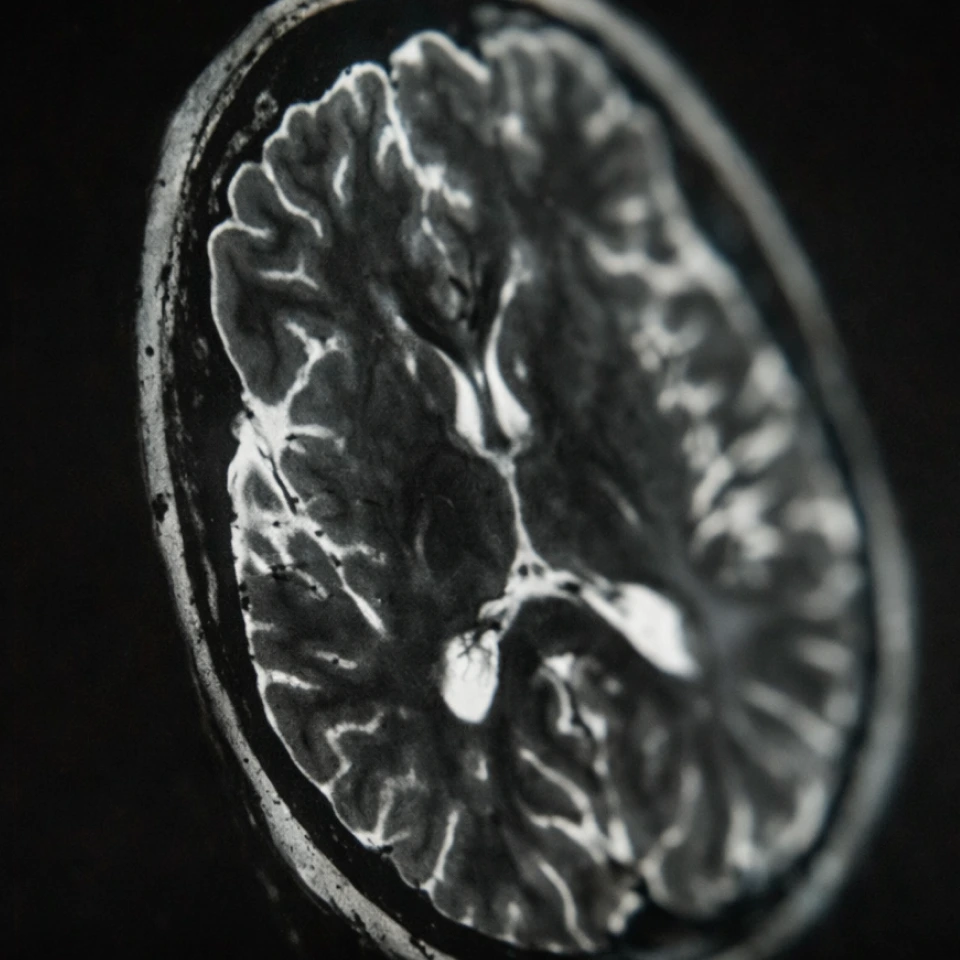

Whole body MRI is one of the leading tools in early detection—capable of helping identify certain abnormalities and other serious conditions before symptoms appear, when treatment is more effective and outcomes are better. It also helps establish a clear baseline for your health—so you can monitor changes over time and make proactive decisions about your care.

2. Research-grade equipment quality

MRI quality isn’t just about machine strength—it’s about the protocols behind the scan.

Prenuvo uses research-grade MRI machines calibrated for whole body imaging that can be done in less than one hour at diagnostic quality. We optimize each scan across several clinical dimensions:

- Voxel count: Higher voxel density = more anatomical detail.

- Tissue weightings and orientations: Multiple contrasts and imaging planes improve the ability to help identify and characterize abnormalities.

- Diffusion imaging: Adds critical information about the tissue environment to help distinguish benign from potentially harmful lesions.